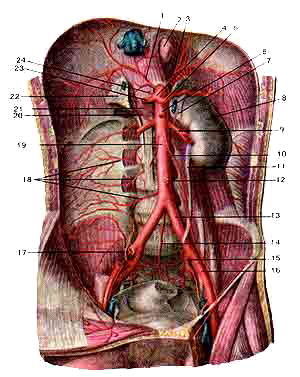

Брюшная часть аорты (aorta abdominalis) и ее ветви

Вид спереди. Желудок, гонкая, толстая кишки и другие непарные opганы, расположенные в брюшной полосой, удалены.1-правая нижняя диафрагмальная артерия;

2-пишевод (отрезан);

3-левая нижняя диафрагмальная артерия;

4-чревный ствол;

5-селезеночная артерия;

6-верхняя брыжеечная артерия;

7-левый надпочечник;

8-левая почка;

9-левая почечная артерия;

11-левый мочегочник;

12-нижняя брыжеечная артерия;

13-левая общая подвздошная артерия;

14-срединная крестовая артерия;

15-внутренняя подвздошная артерия;

16-наружная подвздошная артерия;

17-подвздошно-поясничная артерия;

18-пояснимные артерии;

19-брюшная часть аорты;

20-нижняя надпочечниковая артерия;

21-средняя надпочечниковая артерия;

22-правый надпочечник;

23-общая печеночная артерия;

24-левая желудочковая артерия.